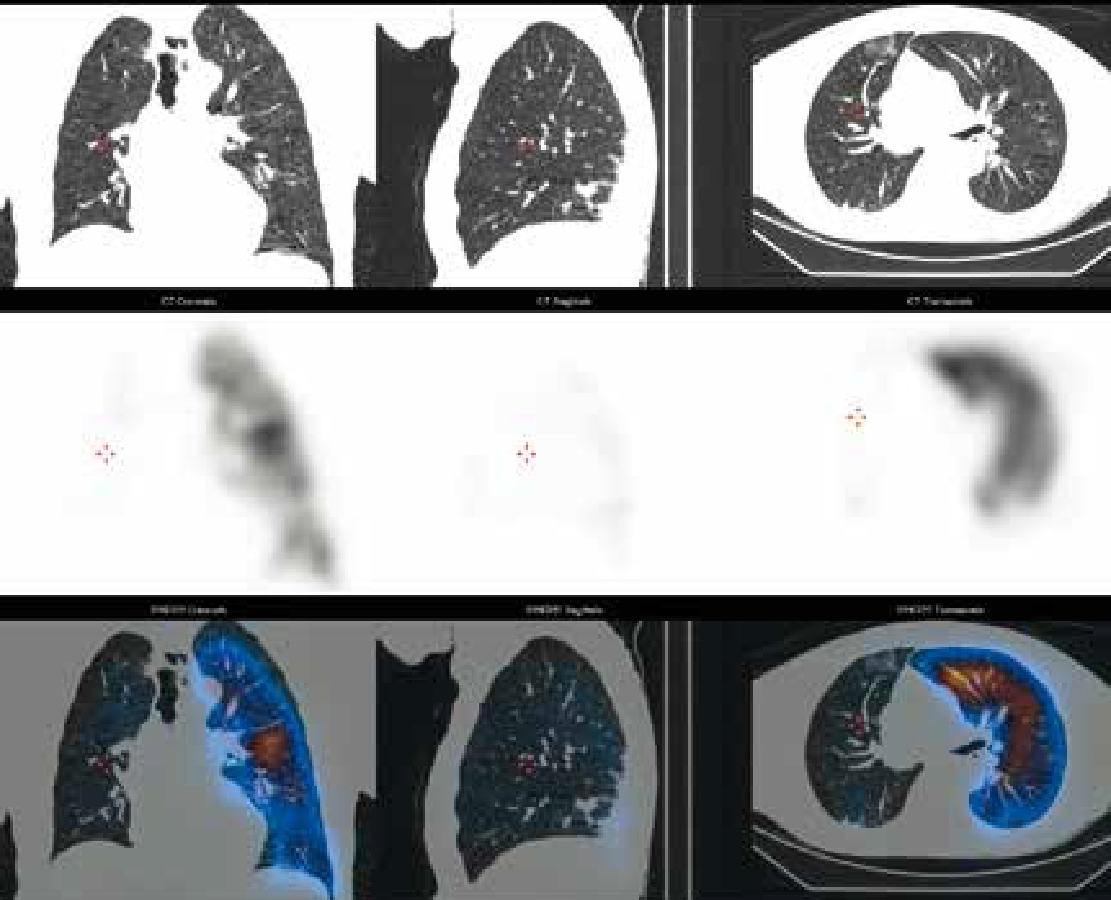

- Перфузионная сцинтиграфия лёгких